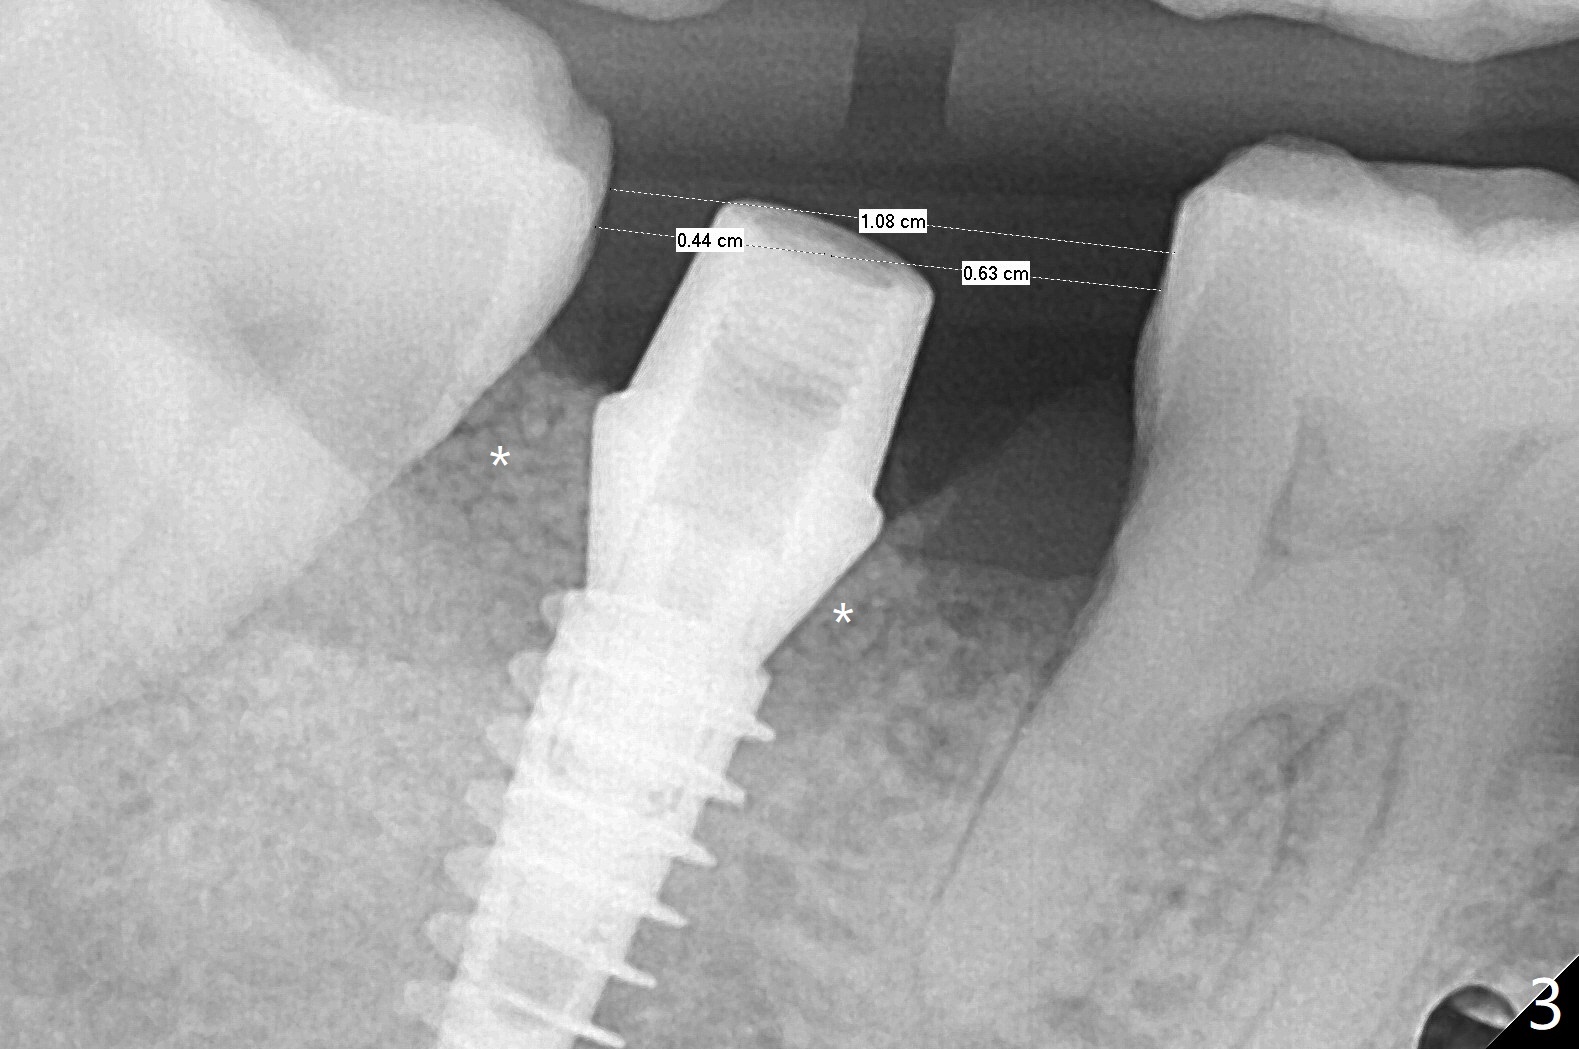

右下7有两个融合牙根,很长,起初(拔除后)有点害怕初步稳定性,使用导板完成近中窝4x10毫米钻洞后,植入4.5x10毫米报废植体,当时没有发觉植体已经发生远中偏移(图一:箭头,因为近中牙槽嵴高(*),而中隔缺失)。当正式植体植入后(图二),病人发现偏移,术者觉得临床上还可以,以为可能因为X光拍摄角度问题。再次放入粘性骨粉后,咬翼片拍摄注意角度问题,但是偏移仍存在(图三)。为了防止偏移现象,要么设计时有意往阻力大的地方偏移少许(例如这个病例1毫米,图四),要么发现偏移后,有意使用侧方切割钻头(Lindamann bur)去除阻力(近中骨)。如果扭力低,包埋植体。术后一个月取出临时牙冠,骨粉仿佛成为牙龈一部分(图五:*),之后暂时粘固粉固定牙冠。术后五个月骨粉好像与邻牙牙根和植体愈合(图六:*)。永久性粘固后,基台螺丝拧紧20Ncm。